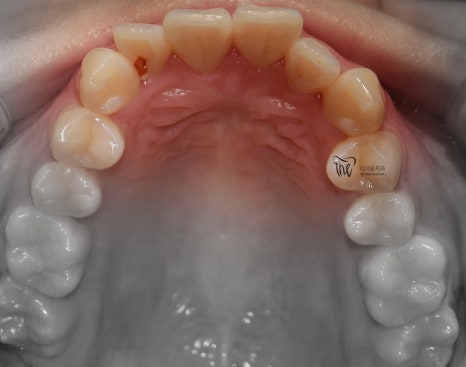

먼저, 임상 사진 5장을 보여드립니다.

그냥 겉으로 봤을 때는 단순 치아들의 불규칙성

때문에 치과에 내원을 하신 것으로 볼 수 있습니다.

그러나, 좌측에서 바라봤을 때는 어금니들이

부정교합을 띄고 있는 것을 볼 수 있습니다.

즉, 거꾸로 물리는 반대교합의 양상을 보여주고

있고 이런 증세 때문에 턱관절의 통증까지도

같이 느끼고 있는 채로 내원을 하셨습니다.